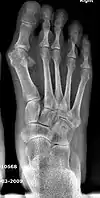

Fig. 5 Stress fracture of the second metatarsal bone

Possible complications

5. Second metatarsal stress fracture (Fig. 5)